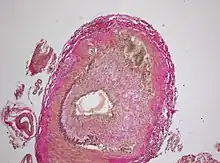

Histopathology of giant cell vasculitis in a cerebral artery. Elastica-stain.

The gold standard for diagnosing temporal arteritis is biopsy, which involves removing a small part of the vessel under local anesthesia and examining it microscopically for giant cells infiltrating the tissue.[23] However, a negative result does not definitively rule out the diagnosis; since the blood vessels are involved in a patchy pattern, there may be unaffected areas on the vessel and the biopsy might have been taken from these parts. Unilateral biopsy of a 1.5–3 cm length is 85-90% sensitive (1 cm is the minimum).[24] Characterised as intimal hyperplasia and medial granulomatous inflammation with elastic lamina fragmentation with a CD 4+ predominant T cell infiltrate, currently biopsy is only considered confirmatory for the clinical diagnosis, or one of the diagnostic criteria.[11]